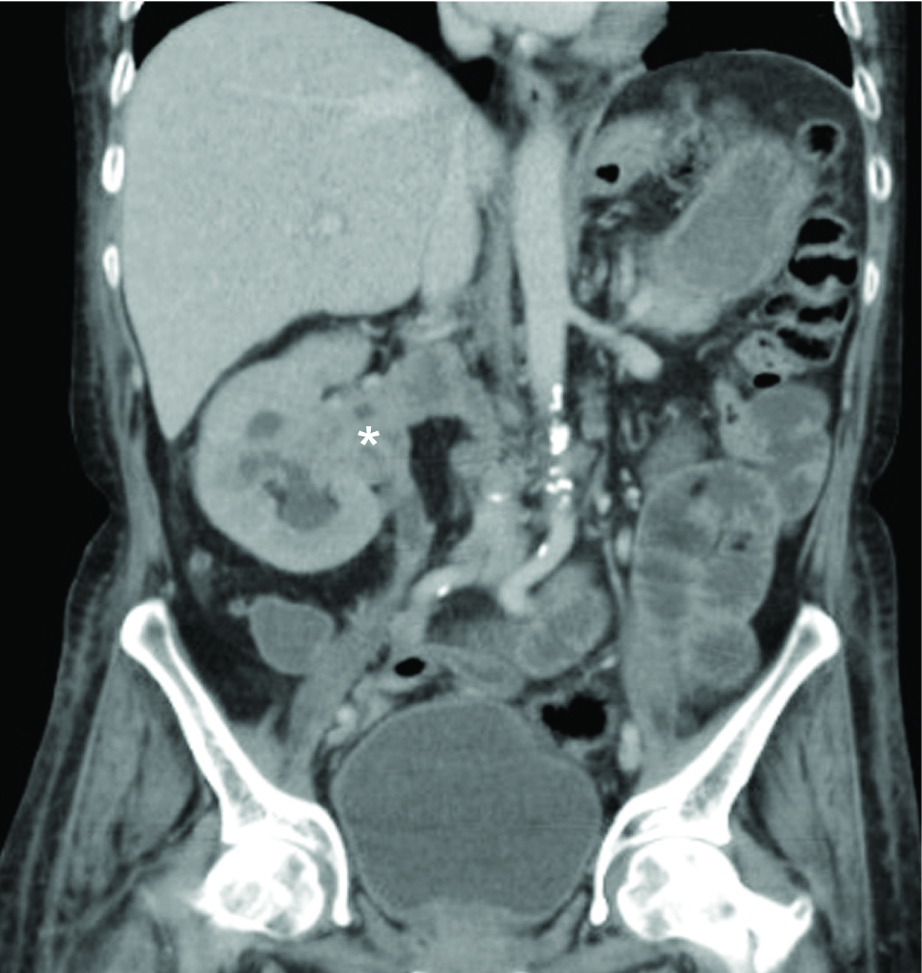

Contrast Enhanced Computed Tomography (CECT) of the abdomen showed a heterogeneously hypo-enhancing soft tissue lesion at the pelvis of right kidney [Table/Fig-1] with malignant para-aortic lymph nodes and a possible left adrenal gland metastasis. Computed Tomography (CT) guided biopsy from the lesion revealed an infiltrating tumor composed of spindle shaped cells with large hyperchromatic pleomorphic nuclei and moderate amount of eosinophilic cytoplasm (high N/C ratio) surrounded by desmoplastic stroma [Table/Fig-2]. Immunohistochemistry (IHC) showed the tumor cells stained positively for Paired box gene 8 (PAX8) and negative for Renal Cell Carcinoma (RCC), Cytokeratins 7 (CK7), Cytokeratin 20 (CK20) and Protein 63 (p63). Hemoglobin electrophoresis showed a normal adult pattern. Diagnosis of Collecting Duct Carcinoma (CDC) was established based on clinical setting, histology and IHC. A percutaneous left renal biopsy was done which was reported as Membranous Nephropathy (MGN) with immunofluorescence positive for IgG1 and negative for IgG4 staining. With the clinical background of an elderly male presenting with Nephrotic Syndrome (NS), a negative immune workup including APLA2R antibodies and renal biopsy suggestive of MGN with absent immunofluorescence staining for IgG4, a diagnosis of disseminated malignancy with secondary MGN was concluded. The nature of the disease and therapeutic options were discussed. Patient and his relatives wished for conservative approach without any definitive surgical or anticancer therapy. Patient was initiated on angiotensin converting enzyme inhibitors with statins and at last follow up, patient continued to have features of NS.

Coronal section of contrast enhanced computed tomography (CECT) of the abdomen showing a heterogeneously hypo-enhancing soft tissue lesion at the pelvis of right kidney (*) extending into the right ureter, calyces, right renal vein and inferior vena cava.